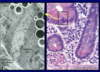

Dashed line surrounds Meissner’s plexus in the submucosa of the alimentary canal. The plexus contains a chain of interconnected neurons. These neurons are described as postganglionic (or postsynaptic) neurons of the parasympathetic division of the autonomic nervous system.

Submucosae (surrounded by the lines) of the esophagus (left) and duodenum (right) are characterized by the presence of the submucosal esophageal and duodenal (Brunner’s) glands, respectively.